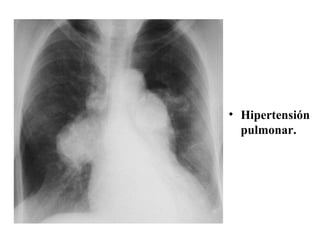

2.  Hipertensión arterial pulmonar  Cuando la  presión sistólica  en la arteria pulmonar  sobrepasa  los  30 mm Hg . Puede ser  debida  a  lesiones  que afectan el  árbol arterial pulmonar , a la presencia de  shunt central  o también  secundario  a la  hipertensión venosa pulmonar . Los  hallazgos   radiológicos   típicos  son la presencia de  dilatación  del  tronco  de la  arteria   pulmonar  y de los troncos de las  dos   arterias   principales  con  estrechamiento  marcado de las  arterias   pulmonares   periféricas .

Hipertensión pulmonar.